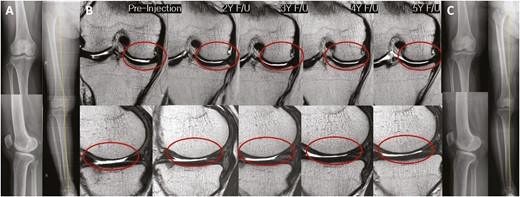

2022年5月14日,韓國江東慶熙大學(xué)醫(yī)院骨科在行業(yè)期刊《干細(xì)胞轉(zhuǎn)化醫(yī)學(xué)》上發(fā)表了一篇關(guān)于《關(guān)節(jié)內(nèi)注射間充質(zhì)干細(xì)胞治療膝骨關(guān)節(jié)炎的安全性和有效性:5年隨訪研究》的研究成果。【4】

招募了11名膝關(guān)節(jié)骨關(guān)節(jié)炎患者,并在單次關(guān)節(jié)內(nèi)注射自體高劑量 (1.0×108?) ADMSCs 的5年隨訪期間進(jìn)行了系列評估。

- 注射后5年內(nèi)未見內(nèi)翻力線或KL等級分布明顯惡化(圖3)。

- 系列MRI檢查顯示,注射后3年內(nèi)MFC軟骨缺損面積呈減少趨勢,治療后5年內(nèi)未見明顯惡化(圖 4)。

- 內(nèi)側(cè)間室軟骨WORMS評分在注射后2至3年間均有明顯改善(2年,P=0.029;3年,P=0.031)(表3)。

- 治療后3年內(nèi),總體WORMS顯示出顯著改善,從73.4±27.8顯著下降至70.5±26.8(6個月;P= 0.020)、65.5±29.4(2年,P=0.016)和66.5±30.7(3年,P=0.041)(表3)。

- WORMS子評分還顯示,在注射后2至3年內(nèi)、注射后2年內(nèi)和注射后3年內(nèi),總軟骨狀態(tài)、骨髓水腫和滑膜炎均有顯著改善。

綜上所述,VAS和總WOMAC評分在注射后6個月以及直到最新隨訪時均顯著改善。總WORMS在注射后3年內(nèi)顯著改善。

單次關(guān)節(jié)內(nèi)注射自體高劑量ADMSCs可在5年內(nèi)提供安全的臨床改善,且不會出現(xiàn)放射學(xué)加重。此外,骨關(guān)節(jié)炎膝關(guān)節(jié)的結(jié)構(gòu)變化在長達(dá)3年的時間內(nèi)顯示出顯著改善,這表明它可能是膝關(guān)節(jié)OA患者的疾病改良治療的一種可能選擇。